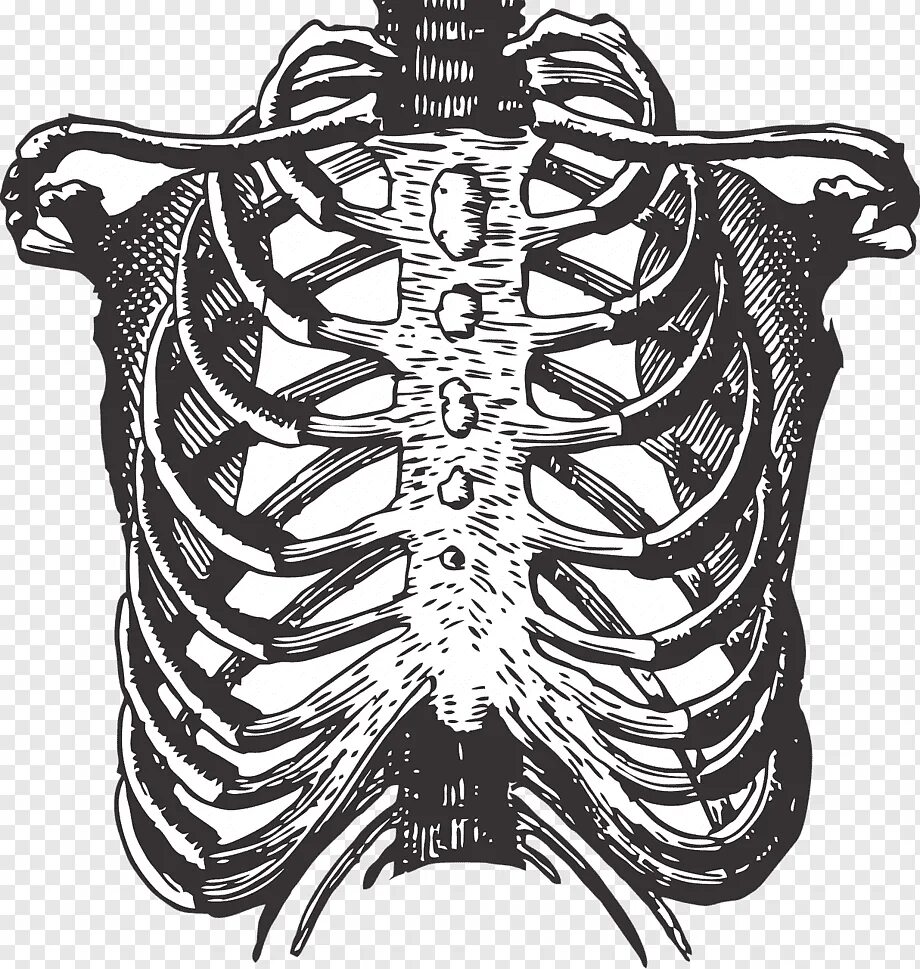

Множественные ребра